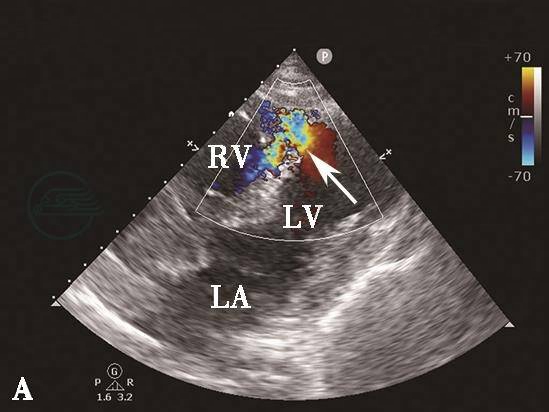

图7心肌梗死二尖瓣乳头肌断裂彩色多普勒血流图像

彩色多普勒血流图像显示二尖瓣乳头肌断裂导致重度偏心性反流(箭头示)。LA.左心房;LV.左心室;RV.右心室。